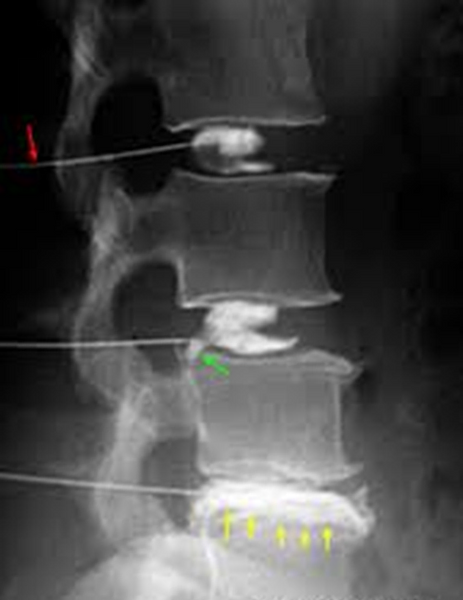

Decided to proceed with Right sided L5 and S1 Transforaminal Epidural Steroid Injections

- 1st on 09/15/2017 > 70% relief of symptom

- 2nd on 10/20/2017 > 80% relief of symptom

- 3rd on 11/21/2017 > 90% relief of symptom

First Lumbar Bilateral L5-S1 Transforaminal Epidural Steroid Injection 11/01/2016 > 30% Relief

Second Lumbar Bilateral L5-S1 Transforaminal Epidural Steroid Injection 11/29/2016 > 50% Relief

Third Lumbar Bilateral L5-S1 Transforaminal Epidural Steroid Injection 12/27/2016 > 70% Relie